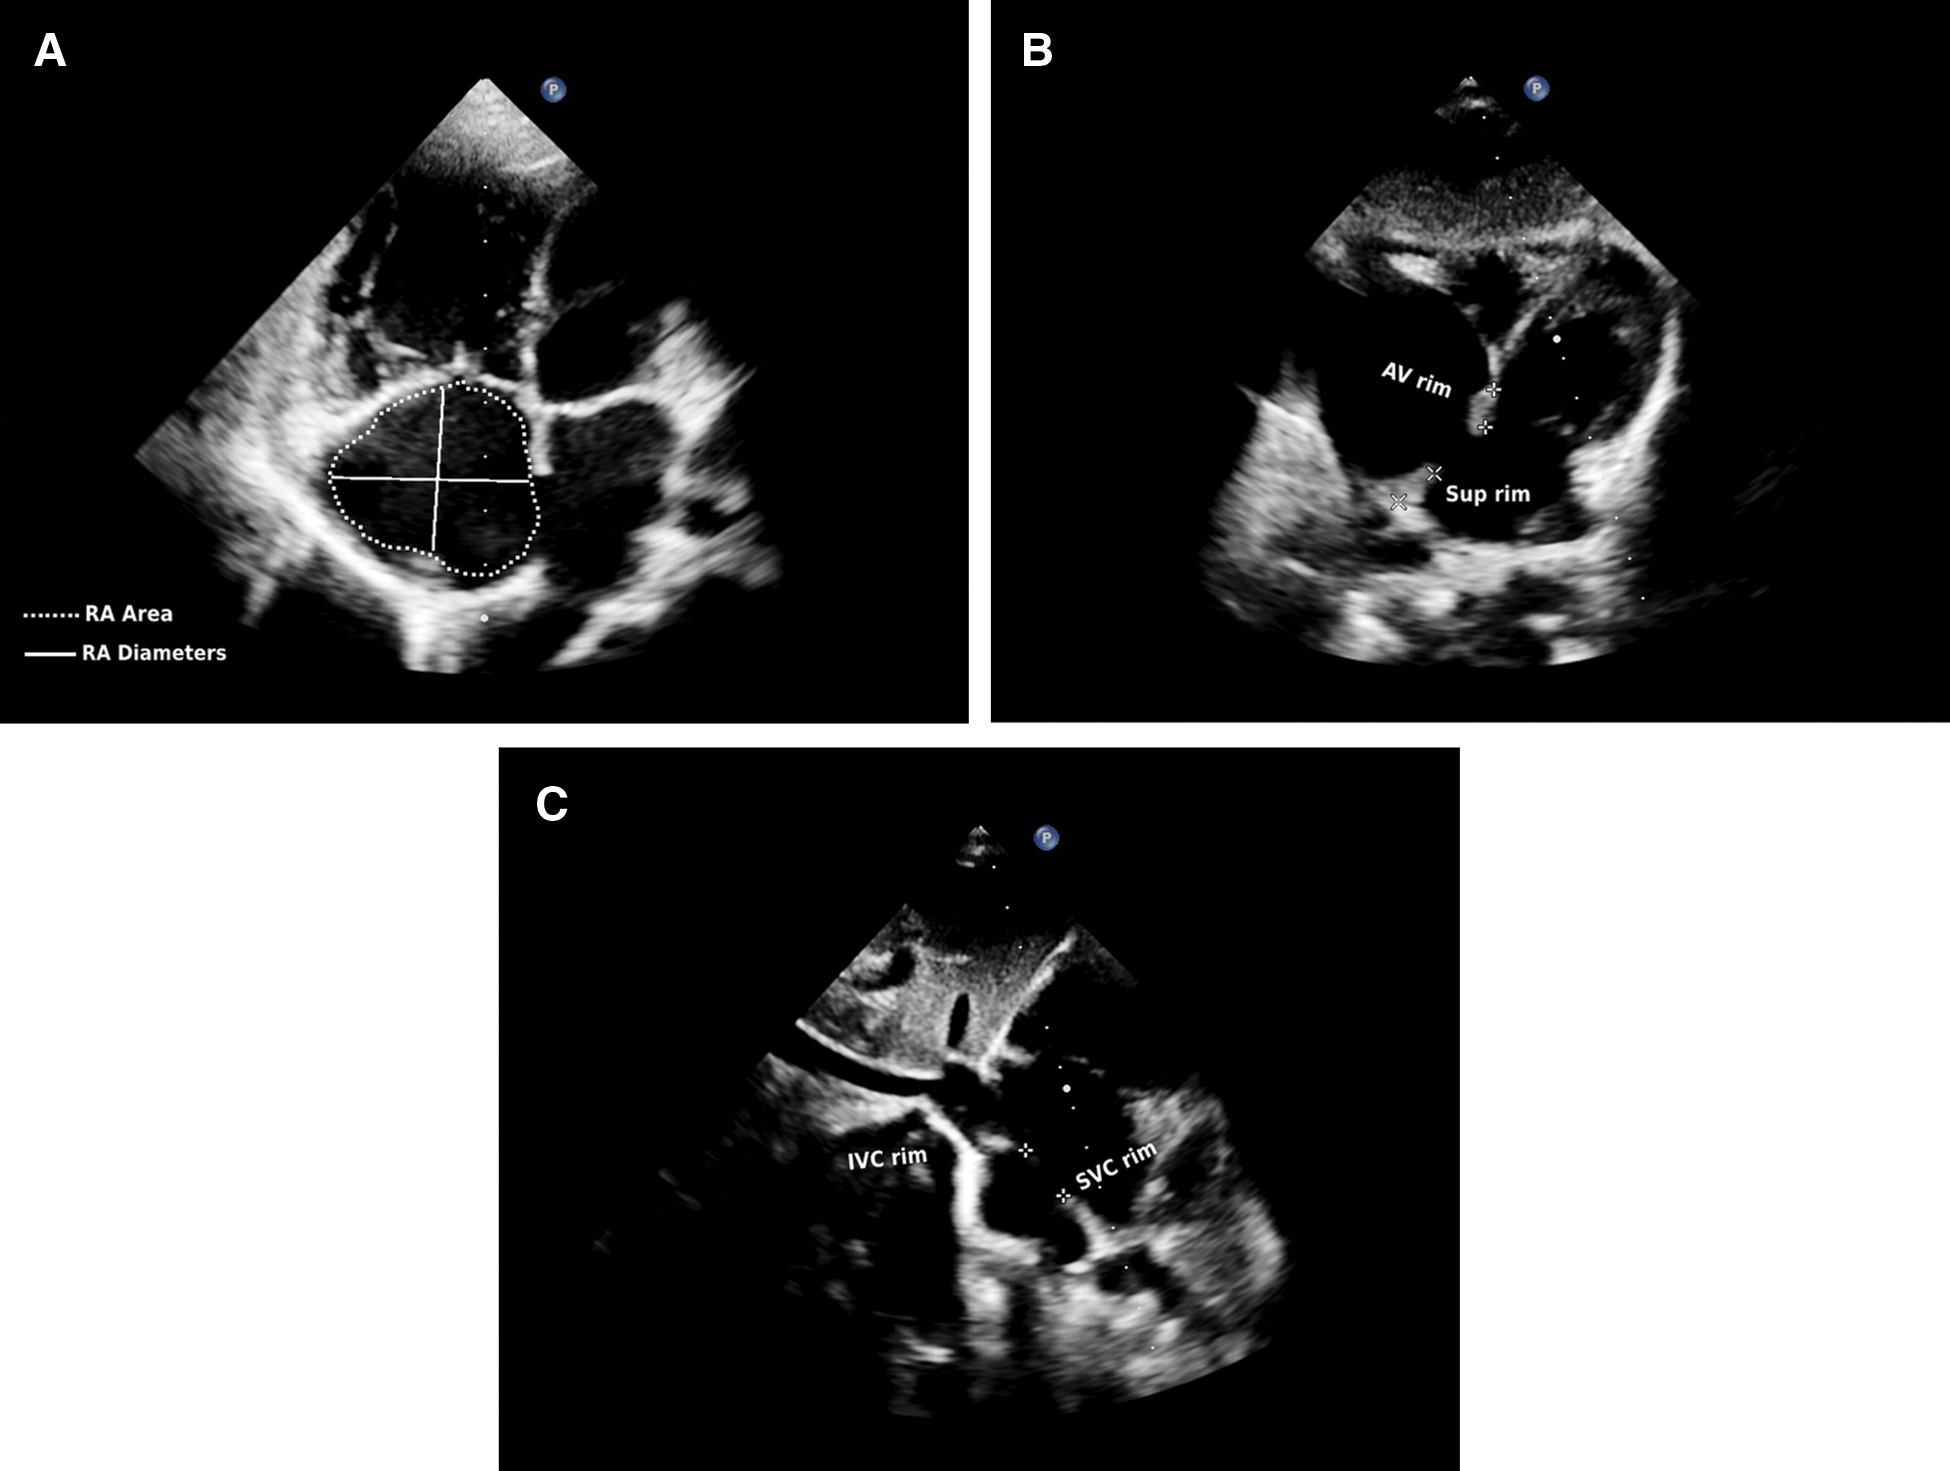

Transthoracic echocardiography (TTE) was performed for all children using the Vivid E9 machine (GE Vingmed Ultrasound N-3191, Horton, Norway). Children with ASD were examined before the procedure, as well as 24 h, 1 month, and 6 months after intervention. ASD and right chambers assessments were performed according to established criteria from the European and American Society of Echocardiography [16–20]. The Qp/Qs ratio was estimated by Doppler measurements of pulmonary and aortic stroke volume [17]. RA dimensions were assessed by RA major and minor diameters while RA area was estimated by planimetry “Figs. 1A–1C”. RV dimensions in the form of RV mid–cavity, RV longitudinal, and RV basal diameters were measured. RV function was assessed using right index of myocardial performance (RIMP) by tissue Doppler (TDI) and tricuspid annular plane systolic excursion TAPSE “Figs. 2A and 2B”. RV systolic pressure (RVSP) and mean pulmonary artery pressure (PAP) were measured. RA volume was calculated as follow: 8/3π (RA area2/RA major length) [16,19]. RA pressure was estimated by inferior vena cava (IVC) diameter and inferior vena cava collapsibility index (IVCCI) in a subcostal view.

Figure 2: (A) Tricuspid annular plane systolic excursion (TAPSE). (B) Right index of myocardial performance by tissue Doppler (RIMP-TDI) (ET; Ejection time, IVCT; isovolumetric contraction time, IVRT; isovolumetric relaxation time) from TTE apical views